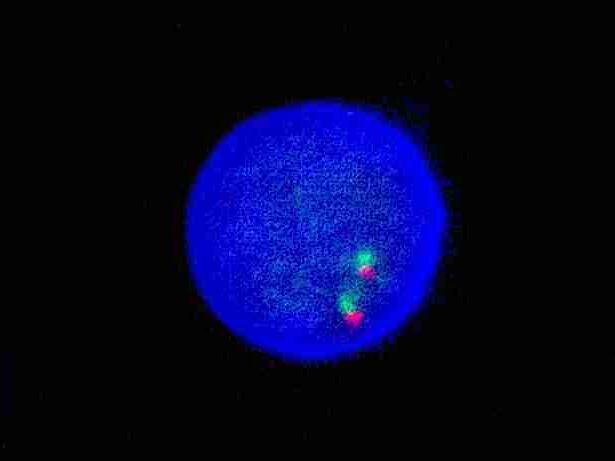

FGFR1 dual color probe

FGFR1 gene 3’ end labeled as orange, with a length of 504 kb; FGFR1 gene 5’ end labeled as green, with a length of 626 kb.